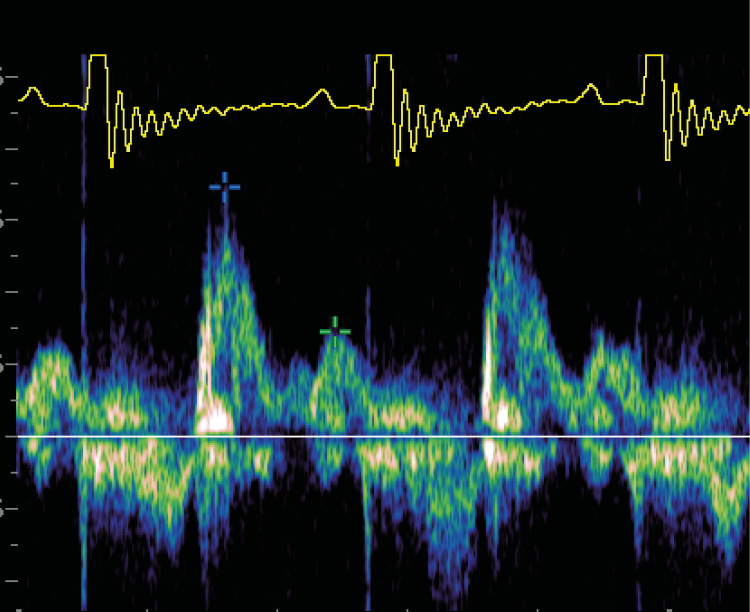

Se añaden dos dosis de hidralazina 0,5 mg/kg/BID por vía oral. Se realiza una ecografía completa y se aprecia: hipertrofia concéntrica de septo interventricular y pared libre ventricular izquierda, atrio izquierdo gravemente dilatado (ratio LA/Ao: 3,02), insuficiencia mitral de 7,5 m/s y disfunción diastólica grado III (imagen 3).

Ecocardiografía con hipertrofia concéntrica difusa de septo interventricular y pared libre ventricular izquierda, grave dilatación de atrio izquierdo, flujo transmitral restrictivo compatible con disfunción diastólica grado III e insuficiencia mitral de alta velocidad que sugiere hipertensión arterial sistémica.

Imagen 3. Ecocardiografía con hipertrofia concéntrica difusa de septo interventricular y pared libre ventricular izquierda, grave dilatación de atrio izquierdo, flujo transmitral restrictivo compatible con disfunción diastólica grado III e insuficiencia mitral de alta velocidad que sugiere hipertensión arterial sistémica.